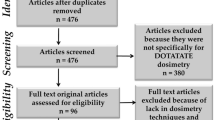

Abstract

The purpose of the EANM Dosimetry Committee is to provide recommendations and guidance to scientists and clinicians on patient-specific dosimetry. Radiopharmaceuticals labelled with lutetium-177 (177Lu) are increasingly used for therapeutic applications, in particular for the treatment of metastatic neuroendocrine tumours using ligands for somatostatin receptors and prostate adenocarcinoma with small-molecule PSMA-targeting ligands. This paper provides an overview of reported dosimetry data for these therapies and summarises current knowledge about radiation-induced side effects on normal tissues and dose-effect relationships for tumours. Dosimetry methods and data are summarised for kidneys, bone marrow, salivary glands, lacrimal glands, pituitary glands, tumours, and the skin in case of radiopharmaceutical extravasation. Where applicable, taking into account the present status of the field and recent evidence in the literature, guidance is provided. The purpose of these recommendations is to encourage the practice of patient-specific dosimetry in therapy with 177Lu-labelled compounds. The proposed methods should be within the scope of centres offering therapy with 177Lu-labelled ligands for somatostatin receptors or small-molecule PSMA.